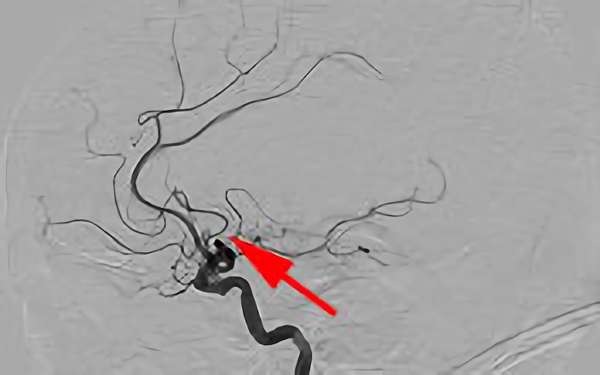

482

'19年5月7日

心原性脳塞栓症

80代

院内外来

'19年5月